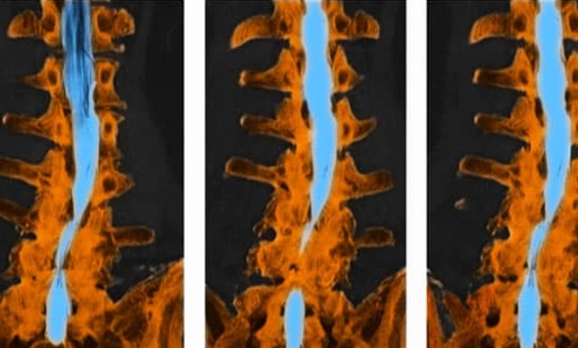

Hẹp ống sống

Sự hao mòn tự nhiên của đốt sống có thể dẫn đến hẹp ống sống. Sự thu hẹp này sẽ gây áp lực lên rễ thần kinh tọa.

Hẹp cột sống phổ biến hơn ở người lớn trên 60 tuổi.

Bác sĩ cũng sẽ yêu cầu chụp MRI để có thêm thông tin về vị trí và nguyên nhân khiến dây thần kinh bị kích thích. MRI cho thấy sự liên kết của đĩa đệm đốt sống, dây chằng và cơ. Chụp CT sử dụng thuốc nhuộm tương phản cũng cung cấp hình ảnh hữu ích về tủy sống và dây thần kinh. Xác định nguyên nhân gây đau thần kinh tọa sẽ giúp hướng dẫn quá trình điều trị.